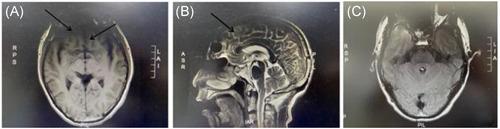

Encephalitis is one of the common diseases in neurology. Early diagnosis and appropriate treatments are essential. Autoimmune encephalitis (AE) generally refers to a type of encephalitis mediated by autoimmune mechanisms. It is gradually considered to be an important cause of reversible encephalitis caused by noninfectious factors. It can occur in children, adolescents, and adults, and is clinically characterized by multifocal or diffuse brain damage such as personality changes, seizures, and cognitive impairment, with an overall good effect of immunotherapy. According to the clinical features of the patients, blood and cerebrospinal fluid tests, neuroelectrophysiology, cranial imaging, treatment and prognosis, AEs can be broadly divided into specific antigen (antibody)-related AEs and nonspecific antigen (or antibody) -related AEs. With the development of AEs research, more and more anti-neuron antibodies have been found, which provides an important reference for the diagnosis and treatment of AEs. Understanding the knowledge about AEs is important to discover new diseases and deepen the understanding of the immunopathological mechanisms of existing central nervous system diseases. Anti-γ-aminobutyric acid B (GABA-B) receptor encephalitis is a type of AE, but this disease is rare in AE, often develop to the clinical manifestations of marginal encephalitis, accompanied by obvious seizures or status epilepticus, Some patients had tumors, mainly small-cell carcinoma, prompt diagnosis, early immunotherapy and, if necessary, tumor treatment resulted in complete or partial neurological improvement in most patients.